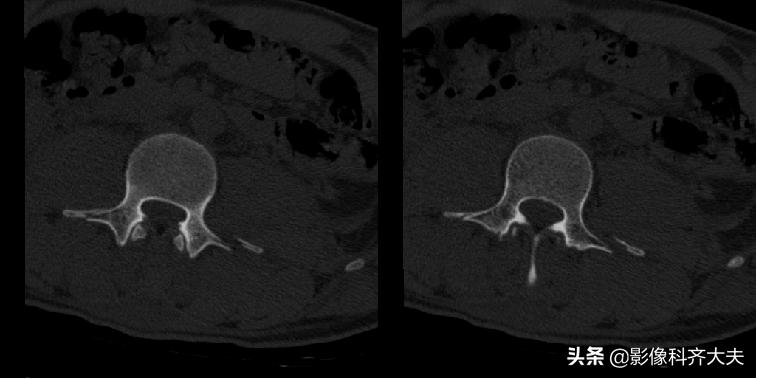

CT检查:

可见骨折椎体内出现横行、纵行、斜行、丫形等形态的骨折线

严重椎体骨折可出现“崩裂”状,表现为多数长短不等骨折线,酷似用力打碎的石板,使椎体分裂成大小不等骨块

椎体后缘骨折,可见游离在椎管内的骨折块大小、形态及位置

当附件骨折X线片显示不清时,CT检查可明确诊断